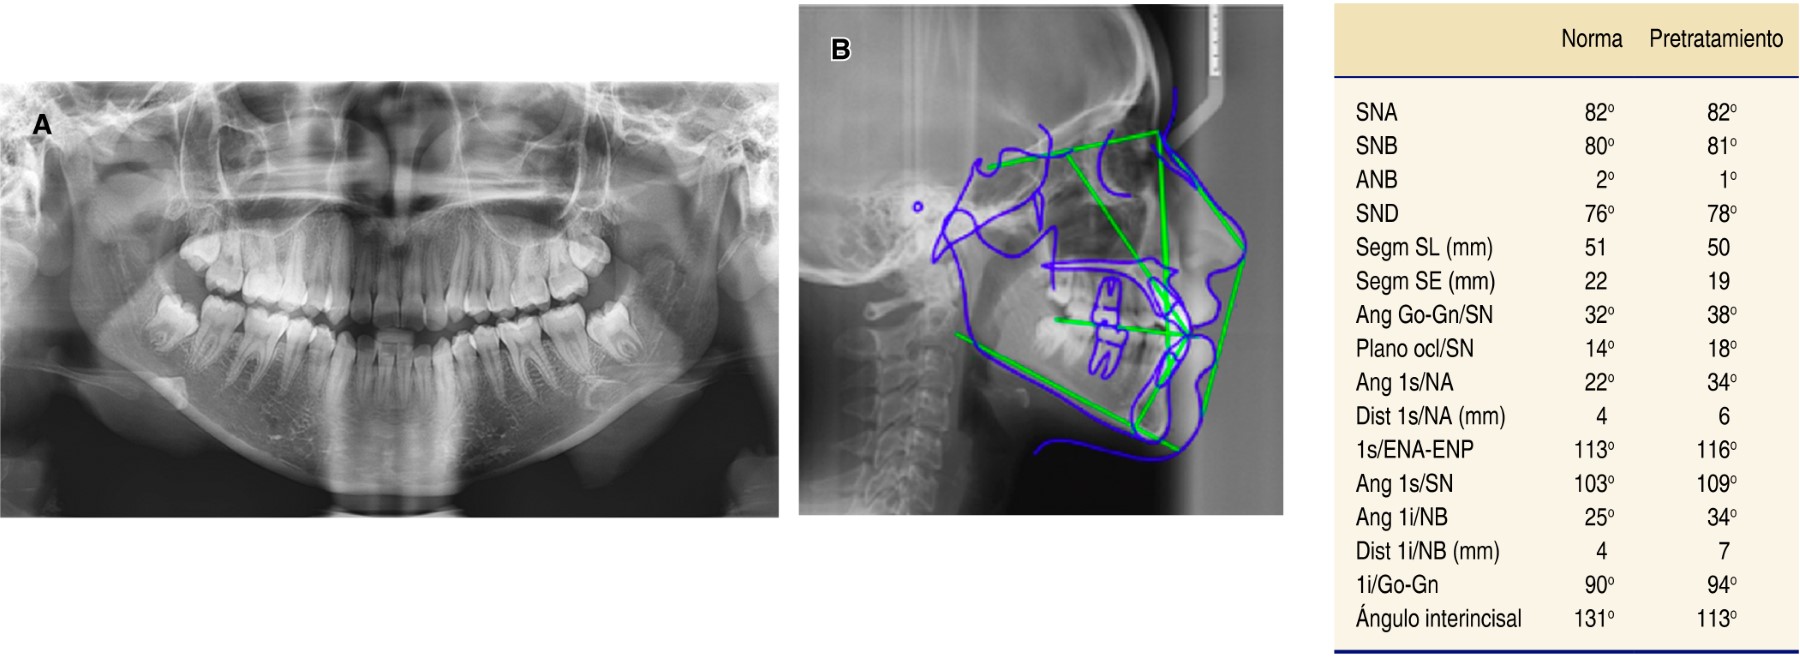

En la radiografía panorámica se observaron 28 dientes permanentes erupcionados y terceros molares en proceso de erupción; la longitud radicular es de 3:1; los senos, cóndilos y ramas mandibulares aparentemente simétricas, sin presentar alguna alteración (Figura 3A).

En la radiografía lateral de cráneo –de acuerdo con el trazado cefalométrico de Steiner– la paciente mostró un patrón esquelético clase I. El plano mandibular aumentado indica un patrón de crecimiento vertical, proinclinación de incisivos superiores (1s/SN 109o) y proinclinación de incisivos inferiores (IMPA 94o) (Figura 3B).

Figura 3